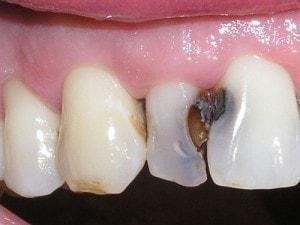

Composite buildup

Tooth #7 is vital

Crown would require root canal and post for retention. Unfortunately, there is no ferrule for a crown.